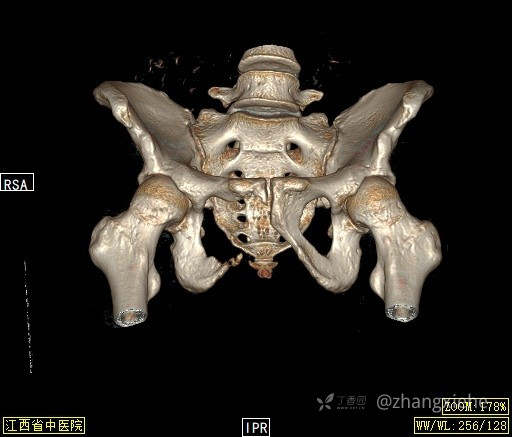

2022-03-05血常规示:血红蛋白:64g/L,生化示:白蛋白20g/L。骨髓涂片细胞学检查示:骨髓增生明显活跃,粒红比减低。粒、红、巨三系增生明显活跃。粒系伴成熟障碍。髓片浆细胞较易见,占7%。粒系增生明显活跃,核明显左移,可见巨幼样变及核浆发育不平衡。PET-CT示:1.右肺下叶软组织肿块、右侧耻骨下支及耻骨联合处骨质破坏伴软组织肿块形成,FDG代谢均异常增改,考虑恶性病变,建议病理检查;右侧髂血管旁、双侧腹股沟淋巴结反应性增生,建议随访。2.多浆膜腔(双侧胸腔、心包腔、盆腔)少量积液。3.全身骨骼FDG代谢弥漫增高,考虑骨髓反应性增生。4.大小肠条片状FDG代谢增高,考虑生理性摄取。5.右侧上颌窦面膜下囊肿,脑部FDG代谢未见明显异常。6.C7-T1层面后纵韧带钙化。患者乏力加重,卧床不起,不能承重,大小便不顺畅,转院至我院。门诊拟“1.右肺占位并右侧骨盆转移2.低蛋白血症3.中度贫血 4,血糖升高(原因待查)”收入住院。患者发病以来,无胸闷、胸痛,无呼吸困难,偶咳嗽,无咳血,饮食、睡眠欠佳,2个月之内体重减轻约10kg。

右骨盆及双下肢未见畸形,皮温正常,无浅静脉怒张,右腹股沟中点可触及一质韧肿物,大小约6cm*4cm*5cm,边界不清,固定、压痛明显,叩击痛阳性。右髋关节外旋、屈曲受限。右髋4字试验阳性,左侧阴性,双下肢直腿抬高试验阴性。感觉、运动正常,末梢血运良好,生理反射存在,病理反射未引出。

诊断?1.肺神经内分泌癌并右骨盆转移 ?2,骨盆透明细胞肉瘤并肺转移?3,多重癌(骨盆透明细胞肉瘤、肺神经内分泌癌) ?